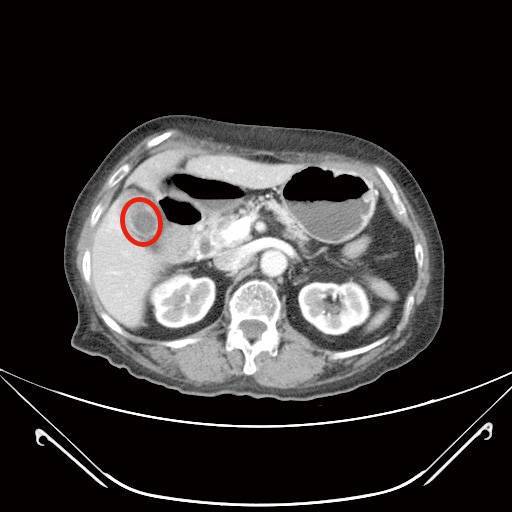

膽囊炎(上圖)

72歲林女士,3年前經上消化道內視鏡檢查發現有個2公分大的胃黏膜下腫瘤,疑似胃腸道基質瘤,持續門診追蹤,近期發現腫瘤緩慢長大,2個月前因上腹部悶痛且頭暈就診,由於合併有血便症狀,經上消化道內視鏡及電腦斷層檢查,發現腫瘤已接近6公分,且膽囊被結石塞滿,沒有膽汁的空間,經過和病人及家屬充分討論,醫療團隊以達文西系統機器手臂輔助腹腔鏡手術,為病人進行部分胃切除以及膽囊切除手術,手術順利,病人於術後第9天出院。病理化驗報告證實胃部腫瘤屬於低度分化惡性胃腸道基質瘤,評估後僅需定期追蹤檢查,膽囊則是慢性膽炎。